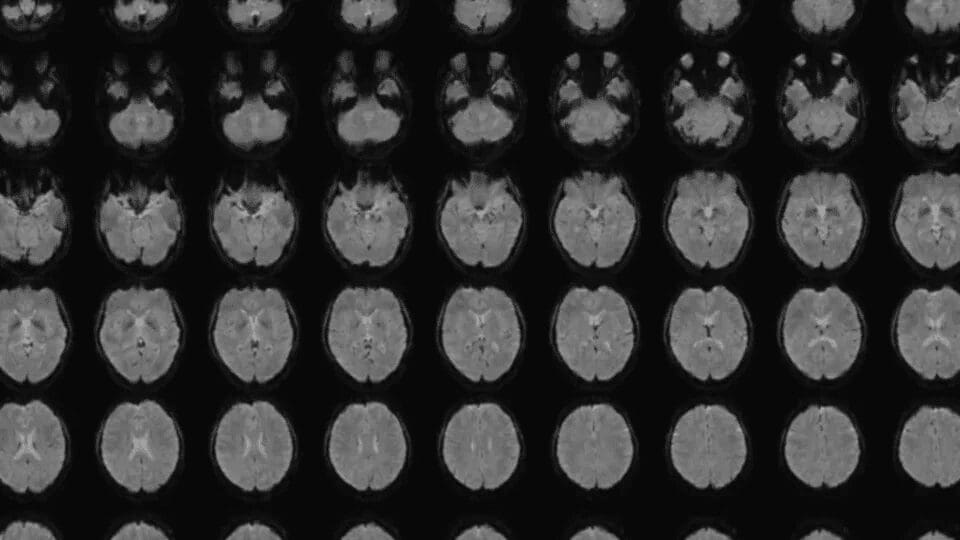

Un nuevo avance tecnológico y neurocientífico en Japón ha captado la atención internacional al lograr convertir imágenes mentales humanas en texto mediante el uso de escáneres cerebrales combinados con inteligencia artificial. El método fue desarrollado por el investigador Tomoyasu Horikawa, quien publicó los resultados el 5 de noviembre en Science Advances, señalando que la herramienta representa un progreso significativo respecto a métodos anteriores que solo habían conseguido transcribir palabras pensadas, mas no imágenes complejas visualizadas o recordadas.

Este nuevo procedimiento fue denominado “mind-captioning” o subtitulación mental y emplea algoritmos avanzados de IA capaces de interpretar información cerebral relacionada con objetos, lugares, acciones, eventos y las relaciones existentes entre ellos. Horikawa explicó que traducir imágenes internas ha sido históricamente más complicado que convertir pensamientos en palabras, debido a la naturaleza multidimensional y asociativa del contenido visual mental.

Para llevar a cabo la investigación, el equipo trabajó con seis participantes —cuatro hombres y dos mujeres japoneses entre 22 y 37 años— empleando escáneres cerebrales mientras observaban 2,180 videoclips sin sonido, con escenas variadas que incluían objetos, ambientes y actividades humanas o animales. La IA utilizó los subtítulos originales de dichos videos para transformarlos en secuencias numéricas, las cuales sirvieron como referencia para modelos de decodificación que correlacionaban los patrones cerebrales con información descriptiva previamente procesada por un modelo de lenguaje generativo.